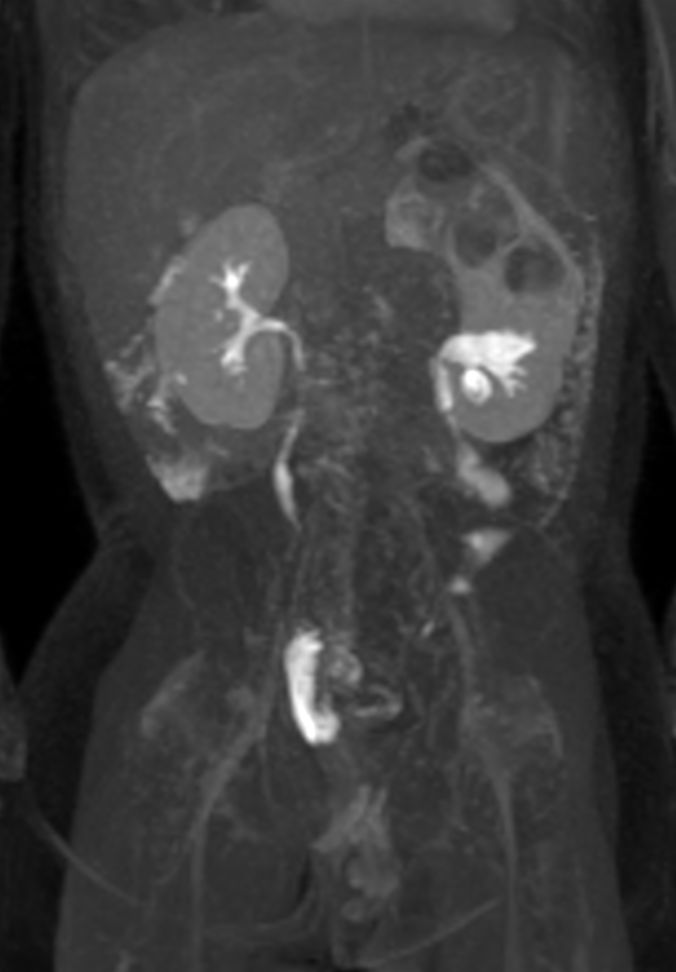

Coronal 3D VIEW T2w SPIR